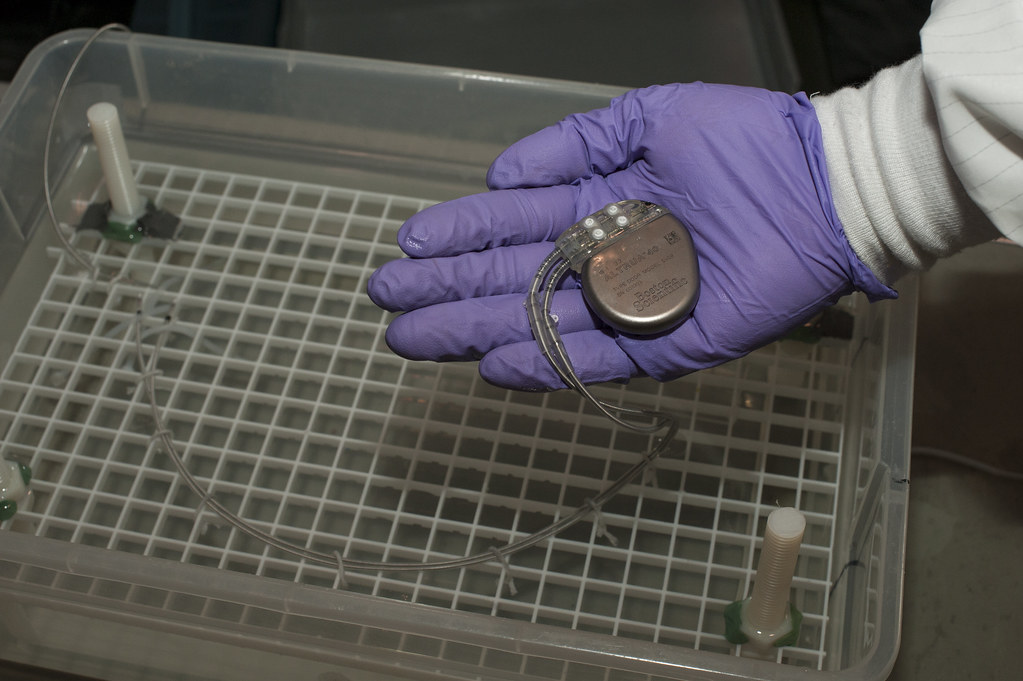

The Pacemaker: A Wrong Component Saved Hearts

In the 1950s, engineer Wilson Greatbatch was building a heart rhythm recording device when he accidentally installed the wrong resistor. Instead of simply recording, the device sent out electrical pulses, mimicking the human heartbeat. This accident led to the creation of the pacemaker, a life-saving device that helps regulate heartbeats in millions of patients today.

At the time, pacemakers were large, external machines. Greatbatch’s version was small enough to fit inside the human body, giving new hope to people with irregular or failing hearts. His accidental discovery has gone on to save millions of lives, and his invention became one of the most important medical breakthroughs of the 20th century.